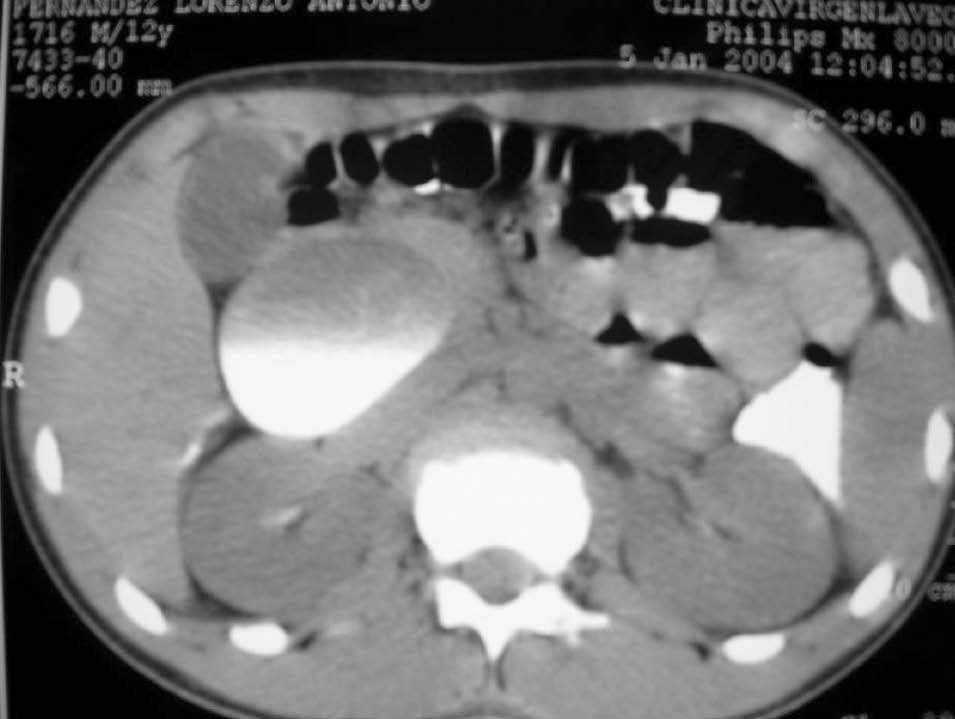

Paciente de 12 años que consulta por dolor en el epigastrio y el hipocondrio derecho de 24 h de evolución. En la exploración se aprecia dolor a la palpación en el epigastrio y el hipocondrio derecho sin signos de irritación peritoneal y discreta distensión abdominal en esa zona. Se realiza una analítica que evidencia leucocitosis (15.000) con desviación izquierda (83 S), elevación de amilasas en sangre y orina (100 y 1.200 UI) y fosfatasa alcalina de 1.121 UI. Se practica ecografía que revela una colesterolosis, un quiste de colédoco de tipo I y signos de pancreatitis aguda asociados. El paciente fue ingresado en planta y presentó mejoría clínica a las 24 h del ingreso. Se realiza un colangiotomografía computarizada (TC) abdominal que confirmó la presencia de un quiste de colédoco de tipo Ia de la clasificación de Todani, de 8,5 cm de diámetro (figs. 1 y 2). A las 48 h del ingreso el paciente presentó un aumento del dolor abdominal, por lo que se practicó una TC abdominal urgente que puso de manifiesto la persistencia del quiste y líquido perihepático y periesplénico, que no había en la exploración anterior, sin signos de necrosis pancreática. Ante la sospecha de perforación del quiste se decidió realizar una intervención quirúrgica urgente. Mediante laparotomía media suprainfraumbilical, se accedió a cavidad abdominal, donde se encontró una peritonitis biliar sin signos de infección. Se aspiraron aproximadamente 2 l de líquido y se lavó profusamente la cavidad peritoneal. Se comprobó la fuga biliar puntiforme en la cara anterior del quiste de colédoco que se encontraba necrosado en su unión con la bifurcación hepática. Se realizaron una colecistectomía reglada y una quistectomía completa, ligando el colédoco normal a su entrada en el páncreas, quedando el límite de la sección proximal en la bifurcación hepática. Se practicó una hepaticoyeyunostomía término-lateral con 2 tutores a ambos conductos hepáticos extraídos con el método de Witzel en el asa en Y de Roux de unos 60 cm de longitud, yeyunoyeyunostomía manual a pie de asa, drenaje tipo Penrose subhepático y cierre de la laparotomía por planos. El paciente evolucionó favorablemente, fue dado alta al décimo día postoperatorio y se encuentra asintomático a los 6 meses de la intervención.

Fig. 1. Colangiotomografía abdominal en la que se observa una gran masa quística de 8,5 cm de diámetro dependiente de la vía biliar extrahepática compatible con quiste de colédoco de tipo I.